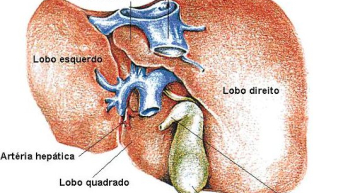

A hipertensão portal recebe esse nome por se tratar de uma questão ocasionada pela intercorrência na comunicação...